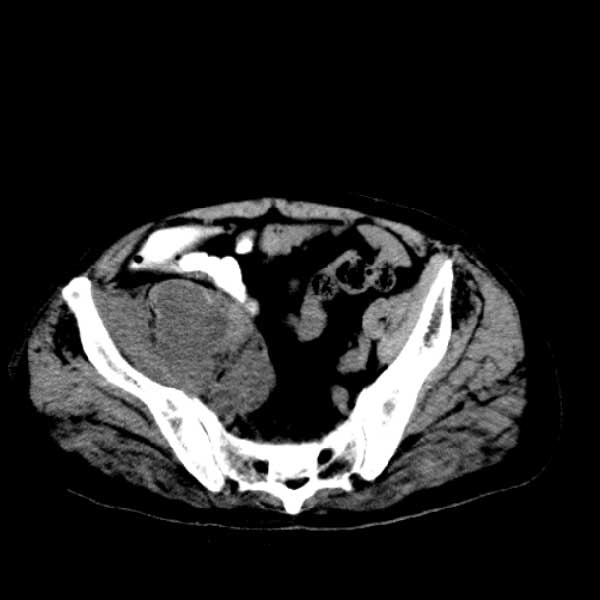

标题: CT13513:男 71 腹部疼痛20余天,近几天高热就诊,骨窗未见异 [打印本页]

标题: CT13513:男 71 腹部疼痛20余天,近几天高热就诊,骨窗未见异

考虑感染性病变可能性大,起源于阑尾?

感染,脓肿形成

考虑为化脓性阑尾炎.脓肿形成.及多肌肉累及.

考虑右侧腰大肌脓肿,向右髂窝、右腹股沟流注。

支持化脓性阑尾炎伴右髂窝脓肿、腰大肌腰方肌脓肿形成。

考虑腹腔及盆腔化脓性炎症,累及右侧髋关节及腹股沟区.

首先考虑化脓性阑尾炎伴腰大肌、腰方肌脓肿,不除外回盲部结核。

回盲部癌待排除。

患者肠镜检查考虑结肠癌,病理证实

患者肠镜检查考虑结肠癌,病理证实。肺部ct可见多发结节,考虑转移